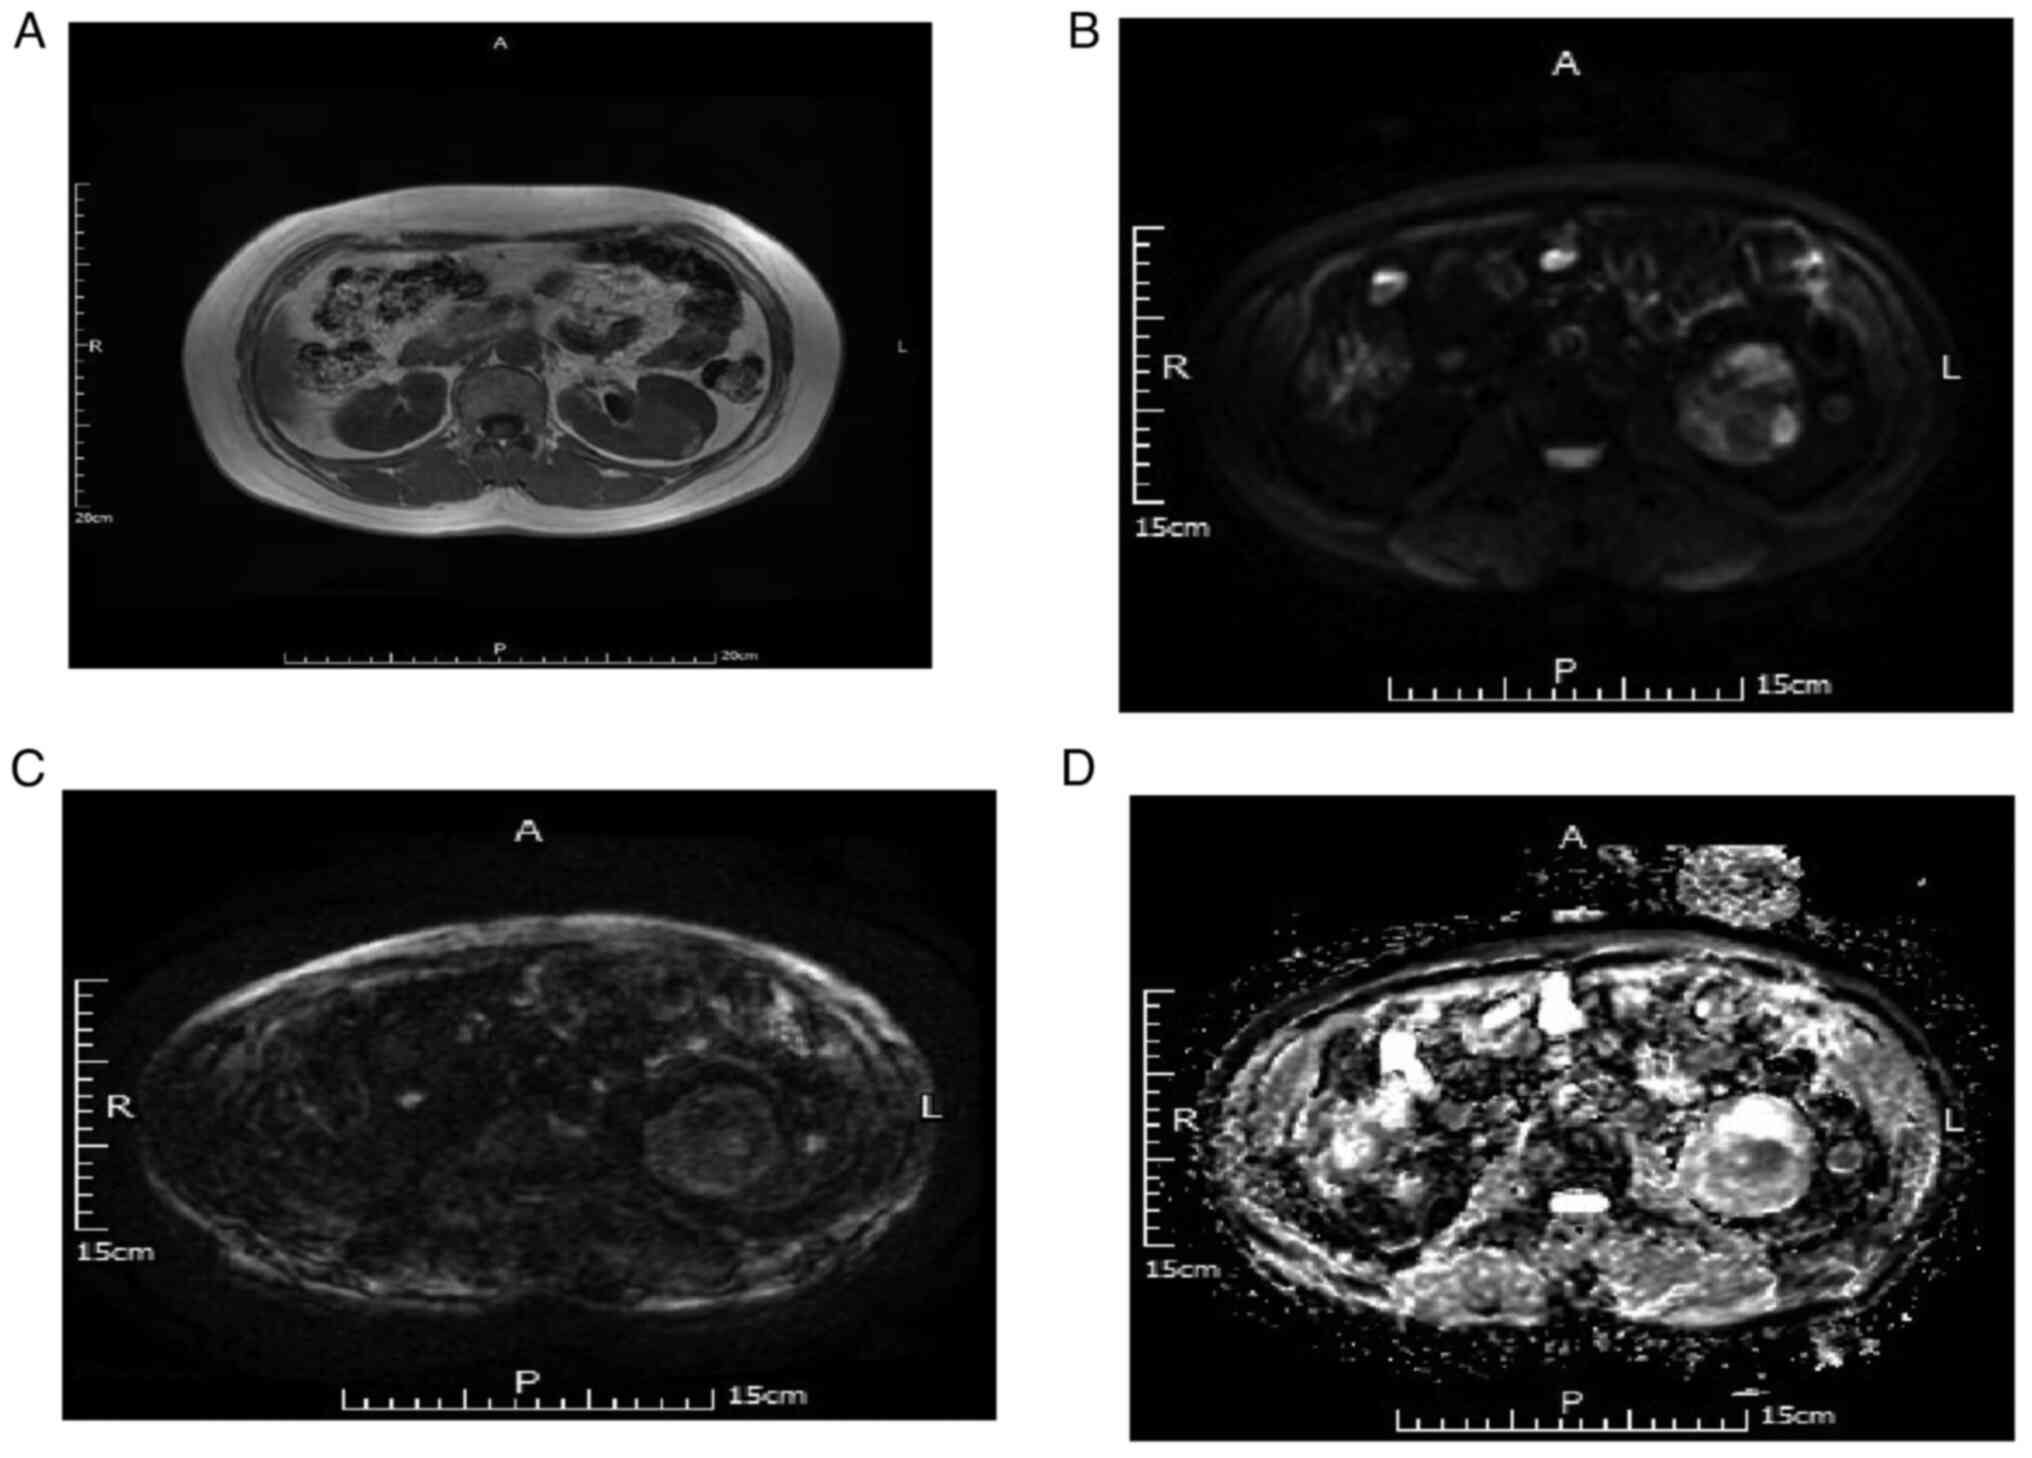

In 11 cases of papillary cell carcinoma, for DWI B-value=50 s/mm2, eight cases (72.73%) were judged as slightly high and three cases (27.28%) as high signal. For DWI B-value=800 s/mm2, two cases (18.18%) were judged as high signal and nine cases (81.82%) as significantly high signal. Additionally, for ADC, three cases (27.27%) were judged as low signal and eight cases (72.73%) as significantly low signal. Representative MRI scans are depicted in Fig. 3.

Figure 3.

MRI scans of a 63-year-old male with pathologically confirmed renal papillary carcinoma of the right kidney. (A) T1WI, right renal tumor with low signal. (B) DWI B=50, right renal tumor with low signal. (C) DWI B=800, right renal tumor with high signal. (D) Apparent diffusion coefficient with low signal. DWI, diffusion-weighted imaging.